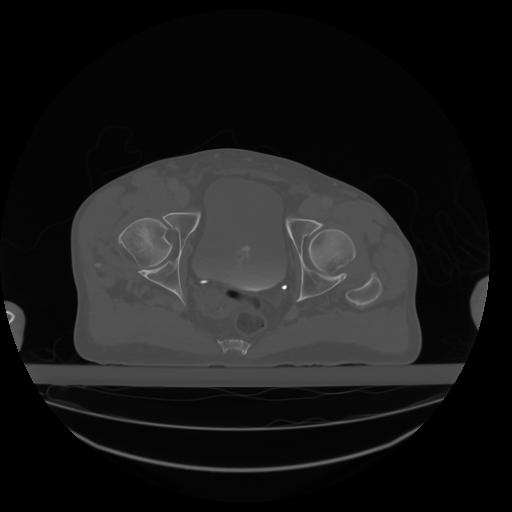

27 CUERPO,CE,Axial,3.0,CUERPO,,